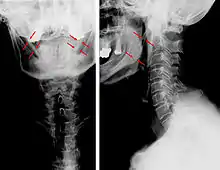

| Anteroposterior and lateral radiographs of cervical spine showing ossification of the stylohyoid ligament on both sides | |

Eagle syndrome occurs due to elongation of the styloid process or calcification of the stylohyoid ligament, potentially compressing the nearby carotid arteryor glossopharyngeal nerve.[4] However, the cause of the elongation hasn’t been known clearly. It could occur spontaneously or could arise since birth. Usually normal stylohyoid process is 2.5–3 cm in length, if the length is longer than 3 cm, it is classified as an elongated stylohyoid process.[10] There are reports of eagles syndrome been elicited after wisdom tooth removal. [11]

Imaging is important and is diagnostic. Visualizing the styloid process on a CT scan with 3D reconstruction is the suggested imaging technique.[12] The enlarged styloid may be visible on an orthopantogram or a lateral soft tissue X ray of the neck.